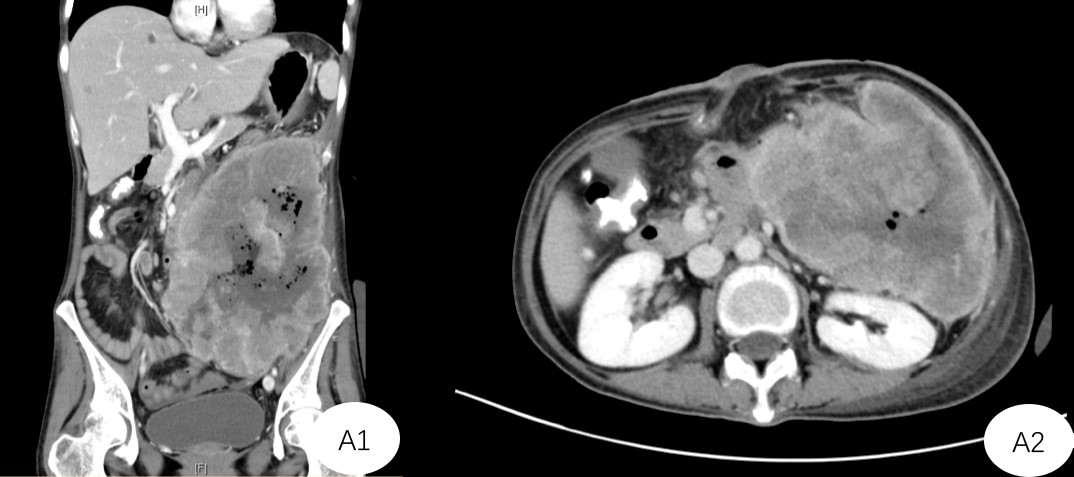

术前诊断:复发性腹腔巨大畸胎瘤、肠瘘、腹壁缺损(因横结肠造口术后出现皮下感染、裂开,加之腹腔感染导致)、重度营养不良。入院后进行腹部CT显示左侧腹腔巨大占位性病变,范围约30*20cm,病灶周围的小肠、肠系膜上血管受挤压移位,肠系膜下血管、左侧结肠被完全包裹在内。肿瘤与胰腺下缘、脾脏下极、多段小肠、腹主动脉、下腔静脉、左侧髂血管、输尿管等重要的器官分界不清,左侧腹壁,部分腰大肌、腰方肌、髂肌也出现受累。

A1+A2:CT提示肿瘤位于左侧腹腔,体积巨大,挤压周边组织、与重要脏器关系不清